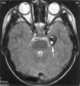

Radiation-induced telangiectasia